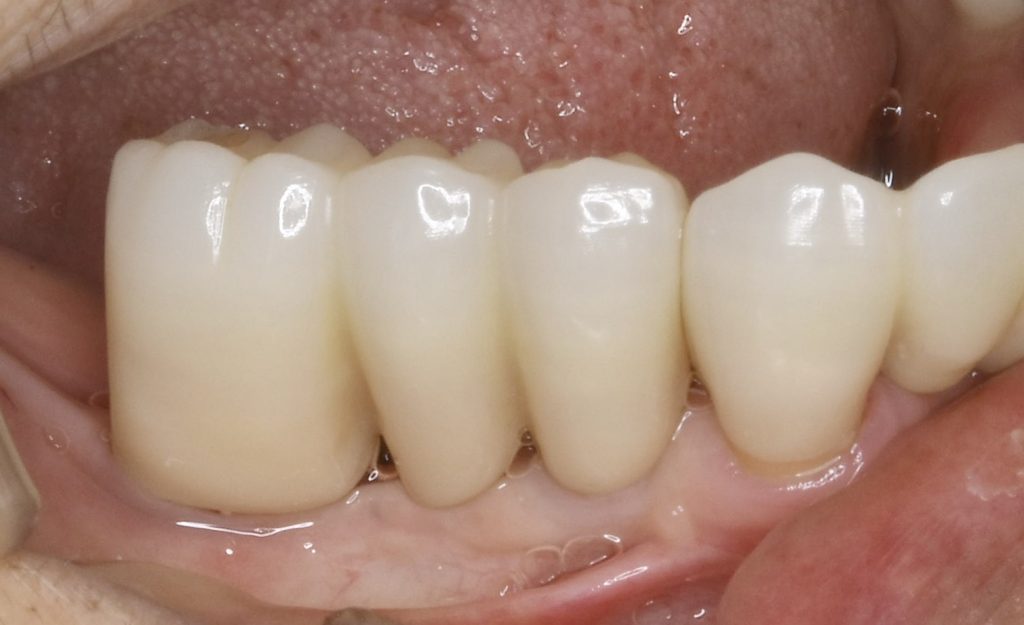

高齢の為、早期の咀嚼機能の回復を目指しショートインプラントを用いた咬合機能の回復を目指しました。

治療後、4年経過しましたが3ヶ月に一度のメンテナンスに来院していただき、しっかり食事が取れるそうで、治療結果に喜んでいただいています。